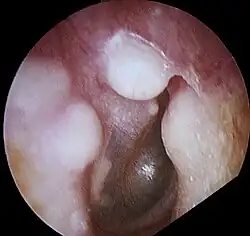

Osteoma of external auditory meatus

An osteoma (plural osteomas or less commonly osteomata) is a new piece of bone usually growing as a benign tumour on another piece of bone, typically the skull. When grown on other bone it is known as "homoplastic osteoma"; on other tissue it is called "heteroplastic osteoma".[1]

Osteoma represents the most common benign neoplasm of the nose and paranasal sinuses. The cause of osteomas is uncertain, but commonly accepted theories propose embryologic, traumatic, or infectious causes. They are present in Gardner's syndrome.